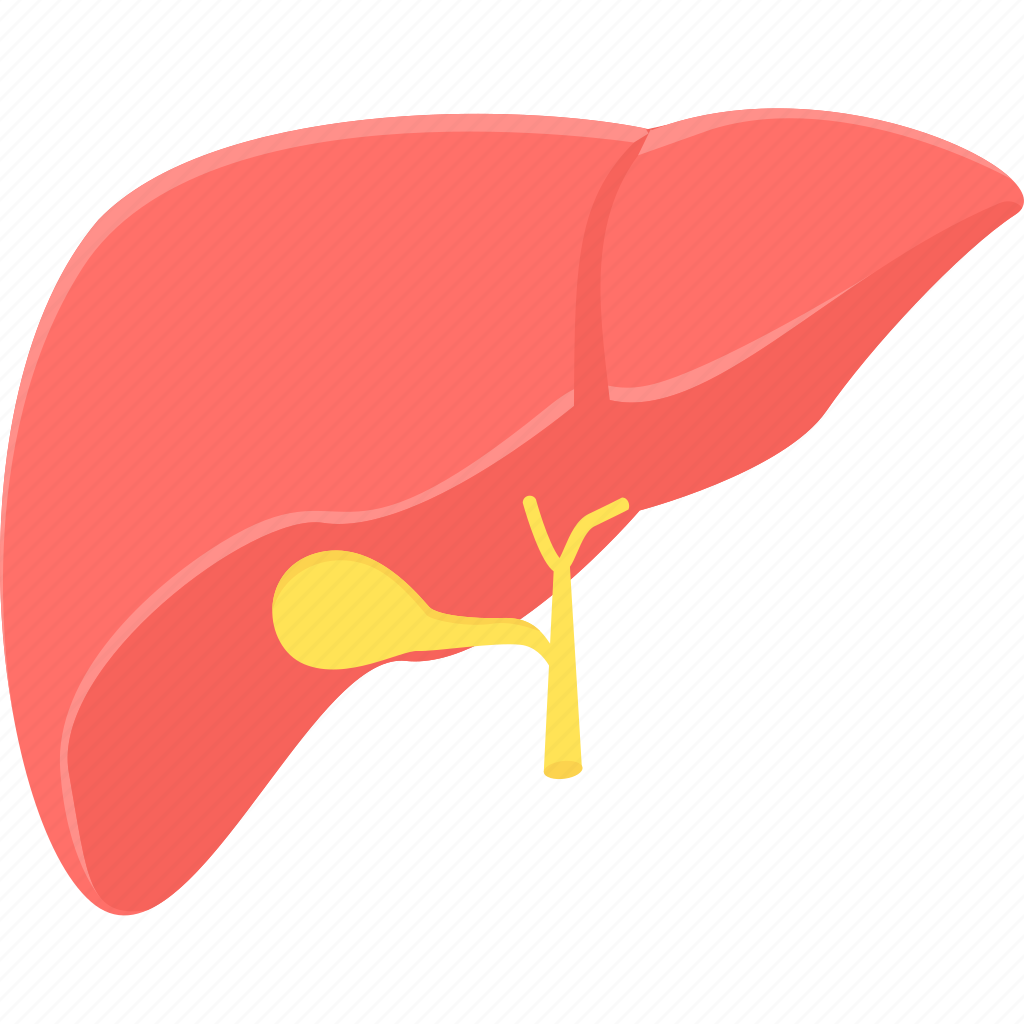

Печень, один из самых крупных и важных органов человеческого тела, выполняет множество жизненно необходимых функций, включая фильтрацию токсинов и производство жизненно важных белков. В данной статье мы рассмотрим, как наглядные изображения печени могут помочь лучше понять её структуру, функции и возможные заболевания. Использование рисунков и диаграмм делает сложные биологические процессы более доступными для понимания, особенно важно это для студентов, врачей и пациентов, стремящихся глубже изучить этот ключевой орган.

Печень рисунок